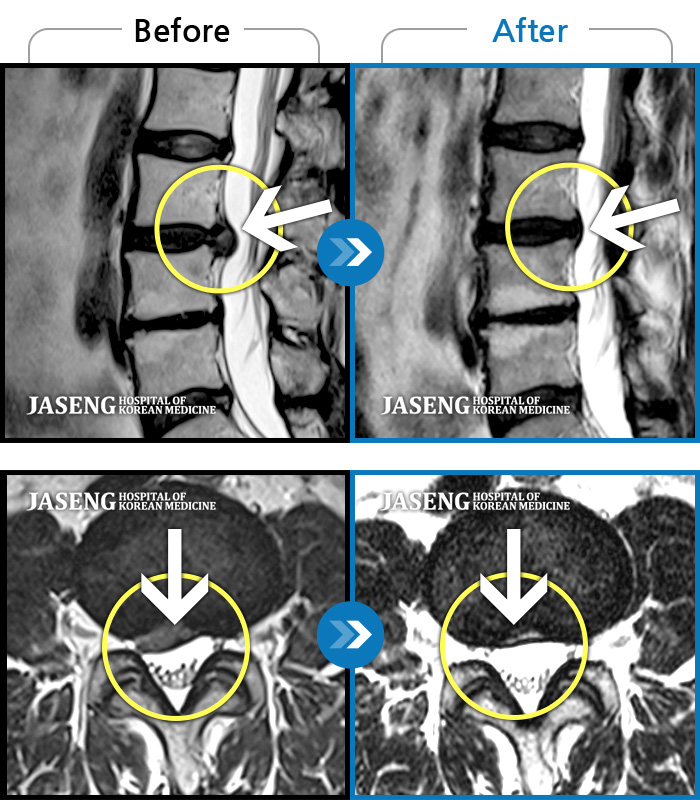

MRI 치료사례

허리 통증과 함께 발끝 저림이 1년 이상 되었으며 최근 1-2개월 사이에 증상이 급격히 심해져 우측 다리 앞 뒤가 당기고 힘이 빠져 본원에 내원함